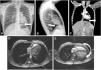

A-C)Radiografía de tórax posteroanterior (A) y lateral (B); TC cardíaca (C); desviación cardíaca hacia la izquierda, con interposición del pulmón entre la salida de la aorta y la arteria pulmonar (*) y presencia de parénquima pulmonar entre el hemidiafragma izquierdo y el margen cardíaco inferior (flecha). D)RM cardíaca con el paciente en decúbito lateral derecho. E)RM cardíaca en decúbito supino mostrando desplazamiento posterior de la silueta cardíaca (flecha).

Presentamos dos pacientes con hallazgo incidental de AdP. El primero fue derivado a los 13años por anomalía de la posición cardíaca en la radiografía de tórax (RxT). Estaba sintomático y no tenía antecedentes personales ni familiares relevantes. Su exploración física era normal. El electrocardiograma (ECG) (fig. 1A) mostraba bradicardia sinusal con desviación del eje del QRS a la derecha (+112°), hemibloqueo de rama derecha (HBRD), desplazamiento a la izquierda de la zona de transición precordial, trastorno inespecífico de la conducción intraventricular (QRS de 96ms) y alteración de la repolarización (ondasT negativas de V1 a V4, transicionales en V5 y positivas en V6). La RxT objetivó interposición del pulmón entre la aorta y la arteria pulmonar (AP), desviación cardíaca hacia la izquierda con pérdida del margen cardíaco derecho y presencia de parénquima pulmonar entre el hemidiafragma izquierdo y el margen cardíaco inferior (fig. 2A-B). Tras la ecocardiografía se sospechó DPP por desplazamiento posterior y a la izquierda del ápex, movimiento septal paradójico y ventrículo derecho aparentemente dilatado por desplazamiento cardíaco hacia la izquierda (fig. 1C; material suplementario vídeos 1 y 2). La tomografía computarizada (TC) y la resonancia magnética cardíaca (RM) confirmaron el diagnóstico (fig. 2C-E). La ergometría fue normal. Debido a que el paciente estaba asintomático, se decidió seguimiento clínico sin complicaciones tras 7años de seguimiento.